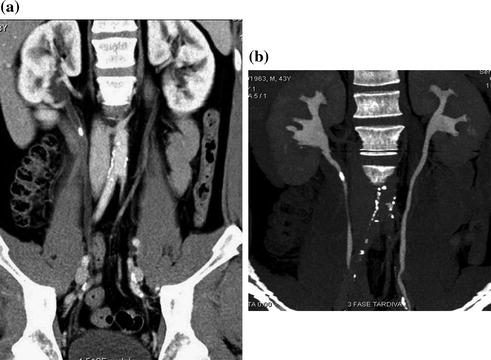

Urography is a medical imaging examination used to evaluate the kidneys, ureters, and bladder. It encompasses various techniques, including excretory urography (also known as intravenous pyelogram or IVP), which utilizes conventional X-rays after intravenous contrast administration, and is still performed for pediatric and some adult patients.

Urography images are instrumental in evaluating and diagnosing a range of urinary tract issues. They provide crucial insights into the health and function of the kidneys, ureters, and bladder, aiding in the detection of abnormalities.

One common use is in the assessment of hematuria, or blood in the urine. Urography can pinpoint the source of bleeding, whether it originates from the kidneys, ureters, or bladder, helping to identify underlying conditions such as kidney stones, infections, or tumors.

Urography is also highly effective in detecting kidney or bladder stones, calcified deposits that can cause significant pain and discomfort. The images can reveal the size, location, and number of stones, aiding in treatment planning and monitoring.

Furthermore, urography plays a pivotal role in the diagnosis and staging of cancers of the urinary tract. It can detect tumors in the kidneys, ureters, or bladder, assess their size and extent, and determine whether the cancer has spread to other parts of the body. This information is essential for guiding treatment decisions and providing prognostic information to patients.